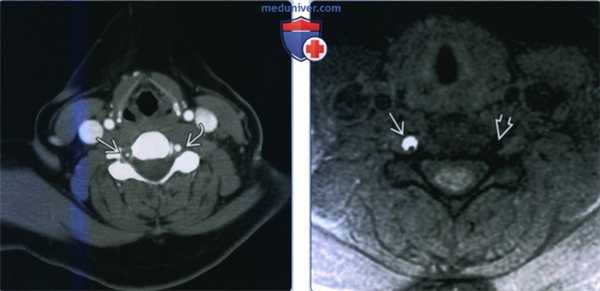

(Слева) КТ-ангиография, аксиальная проекция. Общие сонные артерии и внутренние яремные вены симметричные, имеют нормальный внешний вид. Левая позвоночная артерия проходима, диаметр нормальный. Просвет правой позвоночной артерии резко сужен, а утолщение ее стенки говорит о наличии внутристеночной гематомы.

(Справа) МРТ Т1ВИ FS, аксиальный срез. Состояние после расслоения позвоночной артерии. В стенке правой позвоночной артерии имеется гиперинтенсивный участок в форме полумесяца. Просвет сосуда значительно сужен. Такая картина характерна для внутристеночной гематомы. Обратите внимание на нормальную картину справа: сигнал от правой позвоночной артерии отсутствует.